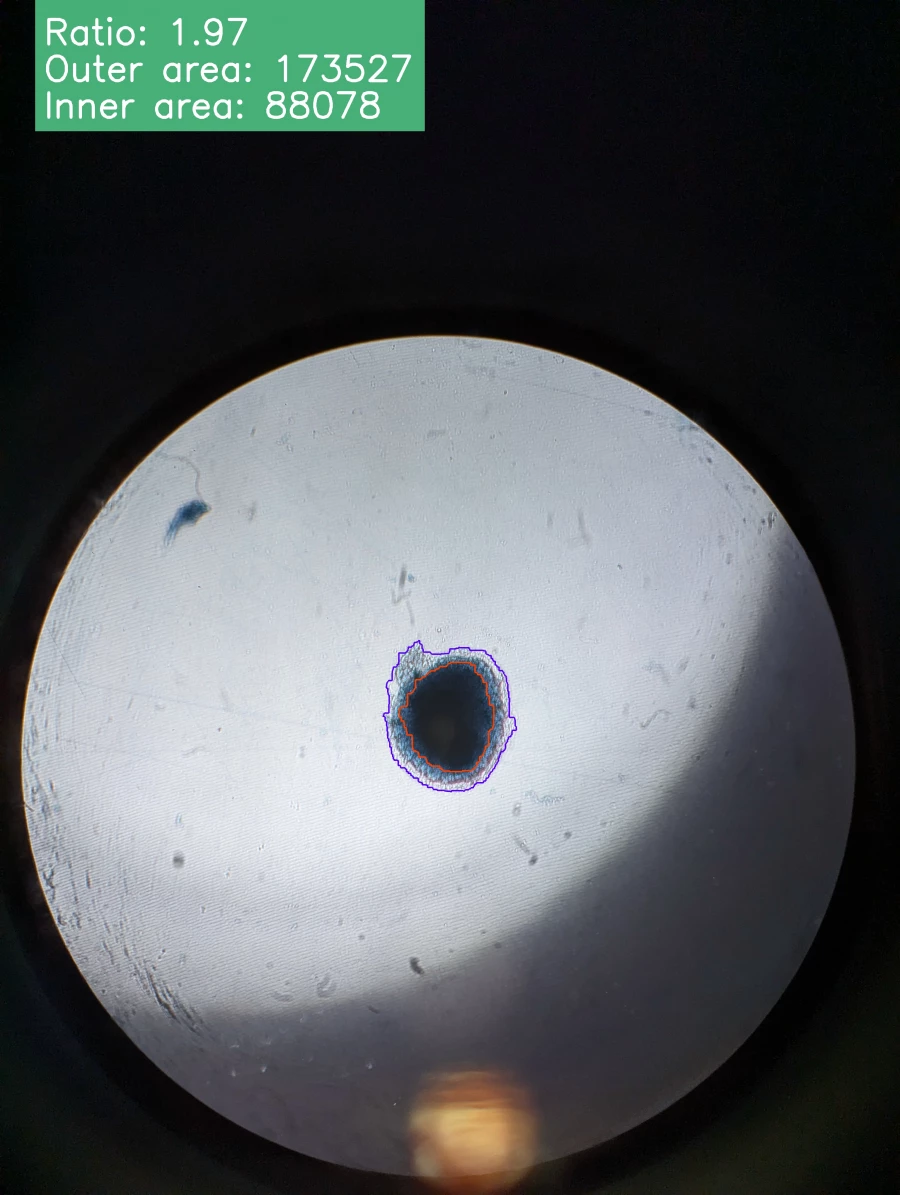

Наука. Снимки эксплантов

Когда эксплант растет в питательной среде, вокруг него формируется так называемая «зона роста» – тонкий, почти прозрачный слой делящихся клеток. Размер зоны – это ключевой показатель жизнеспособности клеток и показывает их реакцию на внешние воздействия, например, на новое лекарство.

Приложение для ученых

Сейчас ученые вынуждены вручную анализировать несколько планшетов с образцами под микроскопом: обводить зоны роста, подсчитывать их площадь. На одном планшете может находиться не менее 24 эксплантов. Это монотонная и трудоемкая работа, напоминает бумажную волокиту и отнимает у лаборантов несколько дней, которые они могли бы посвятить исследованиям.

«Мы создаем автоматизированную систему для анализа изображений эксплантов, – рассказывает Михаил Макеев. – Пользователь сможет загружать снимки на наш онлайн-сервис. Затем алгоритм на основе машинного обучения автоматически распознает и обводит эксплант и зону роста. После этого он проводит все необходимые расчеты и выдает готовый отчет. Это освободит время для более сложных научных задач».